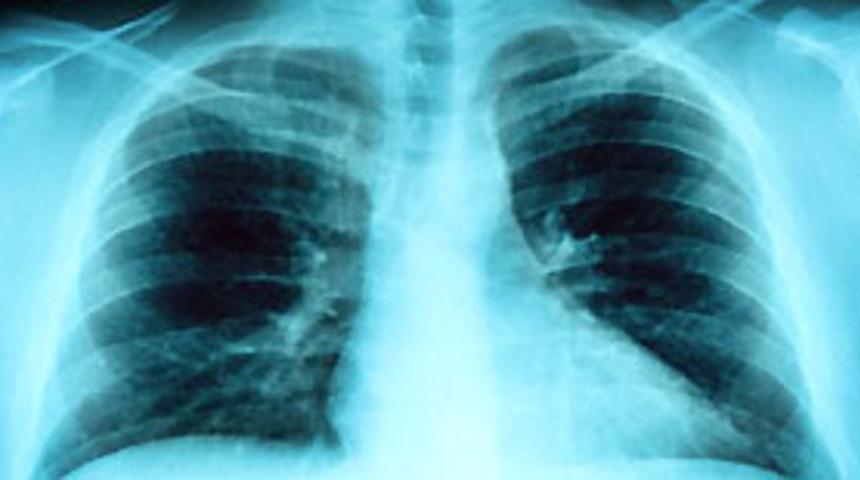

Akciğer kanseri tedavisinde yeni yöntemler

Akciğer kanseri tedavisi, göğüs hastalıkları, göğüs cerrahisi, onkolog, radyoterapist, radyolog ve patolog hekimlerin ortak kararına göre yapılır. Akciğer kanserinde, son yıllarda yeni uygulanmaya başlayan tedavi yöntemleri de vardır.